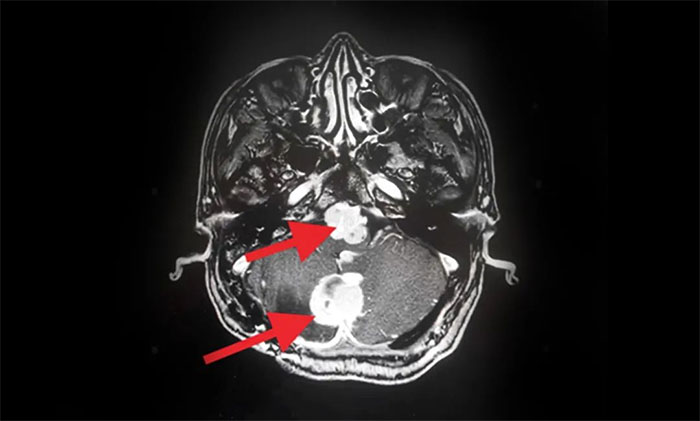

2019年,出現(xiàn)頭痛等癥狀后再次就醫(yī)。查頭顱MRI提示:多發(fā)性腦腫瘤,考慮小腦血管母細(xì)胞瘤術(shù)后復(fù)發(fā),基因檢測(cè)提示VHL(Von Hippel-Lindau,希佩爾- 林道綜合征),后采取保守治療。

▲ MRI影像提示多發(fā)腦腫瘤

入院后,腫瘤科(放療)頭部伽瑪?shù)督M主任陳琦為他完善了MRI檢查,明確多處腫瘤的位置、體積(單體腫瘤最大直徑約2.7cm)。經(jīng)與神經(jīng)外科、醫(yī)學(xué)影像科等開展MDT多學(xué)科聯(lián)合會(huì)診,評(píng)估復(fù)發(fā)腫瘤病灶毗鄰腦干等重要功能區(qū),手術(shù)難度高、風(fēng)險(xiǎn)大,可通過頭部伽瑪?shù)吨委煟刂颇[瘤生長(zhǎng),快速緩解臨床癥狀。